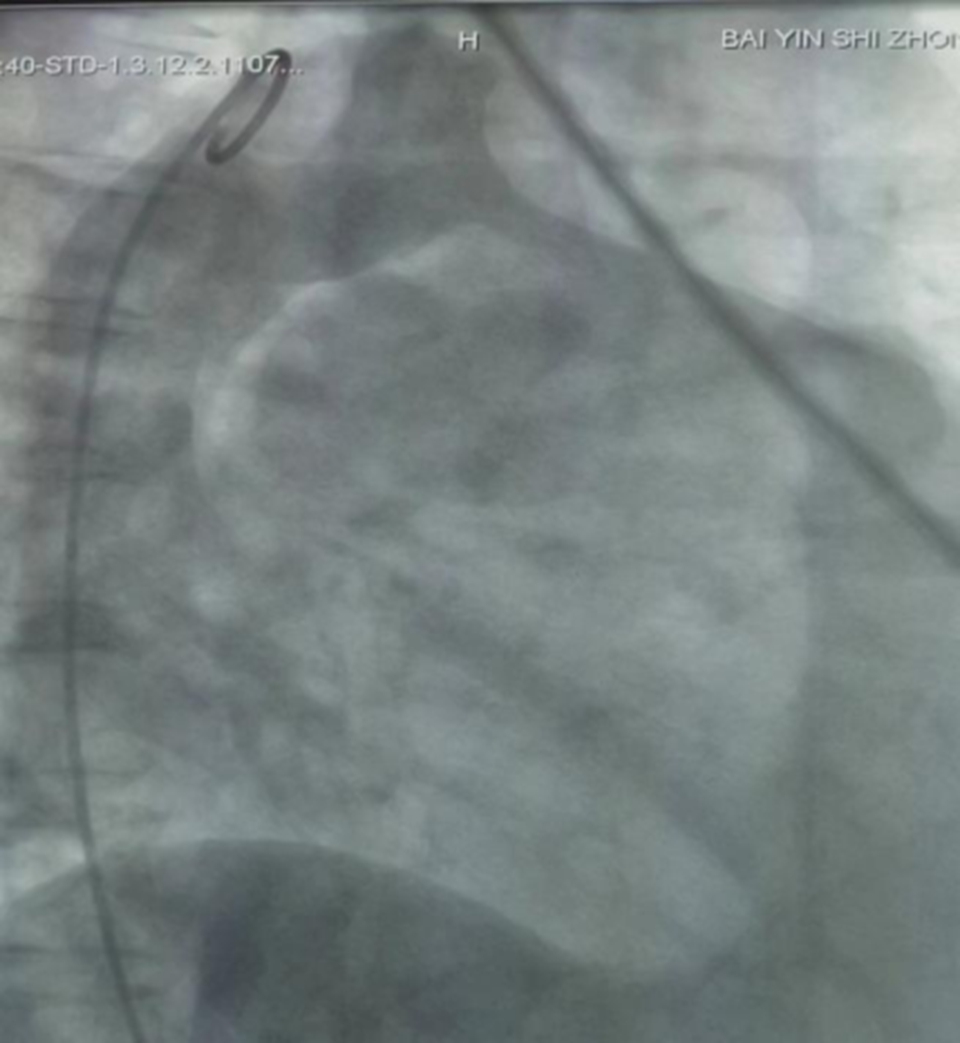

3月1日,副院长赵芳带领心内科介入团队,成功完成我院首例动脉导管未闭介入封堵术,术后患者心脏杂音消失,恢复良好。

手术采用一根导管穿刺大腿根部的股静脉、股动脉,建立通路,沿此途径将封堵器传送到缺损或畸形通道的部位,将缺损堵闭即完成手术,手术时间约0.5~2小时。对于房间隔缺损、室间隔缺损,动脉导管未闭畸形,动脉导管未闭介入封堵术一种非常有效的治疗方法,与传统外科开胸手术治疗相比,具有手术简单、伤口小、恢复快、并发症少等优点。先心病介入治疗覆盖的病种中,近99%的PDA(动脉导管未闭)、70%~80%的ASD(房间隔缺损)、70%以上的VSD(室间隔缺损)患者均可经介入治疗达到治愈。